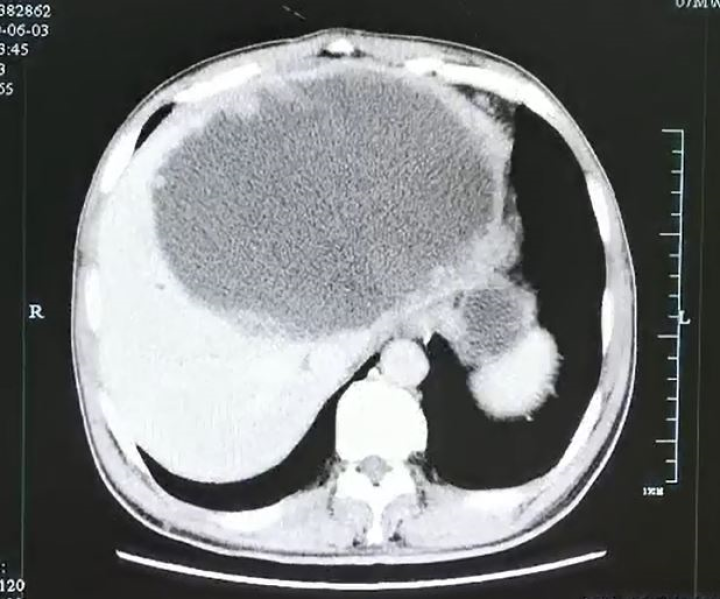

健康|吓人!男子左肝被"掏空",壁上布满虫卵!罪魁祸首竟是…

【健康|吓人!男子左肝被"掏空",壁上布满虫卵!罪魁祸首竟是…】本文专家:王思露,国家高级食品检验师,中华人民共和国HACCP食品体系内部审核员

杭州的谢师傅

由于进食了

未完全加热成熟的酸菜鱼

而感染了“华支睾吸虫”